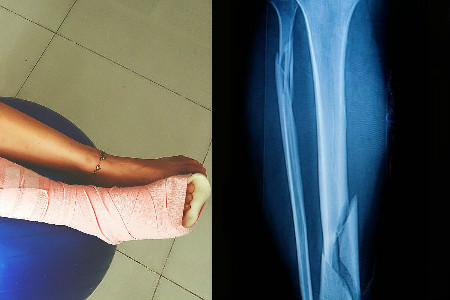

腿部骨折所需的恢复时间一般都很长,正所谓伤筋动骨一百天,很多涉及到骨头的伤病都需要很长一段时间来恢复。如果腿部骨折比较轻微,只是稍微的脱臼或骨骼错位,那一般三个月左右就差不多能下地走路了。如果症状比较严重,骨骼错位严重,那恢复的时长可能就需要半年的时间,甚至更久才能下地走路。